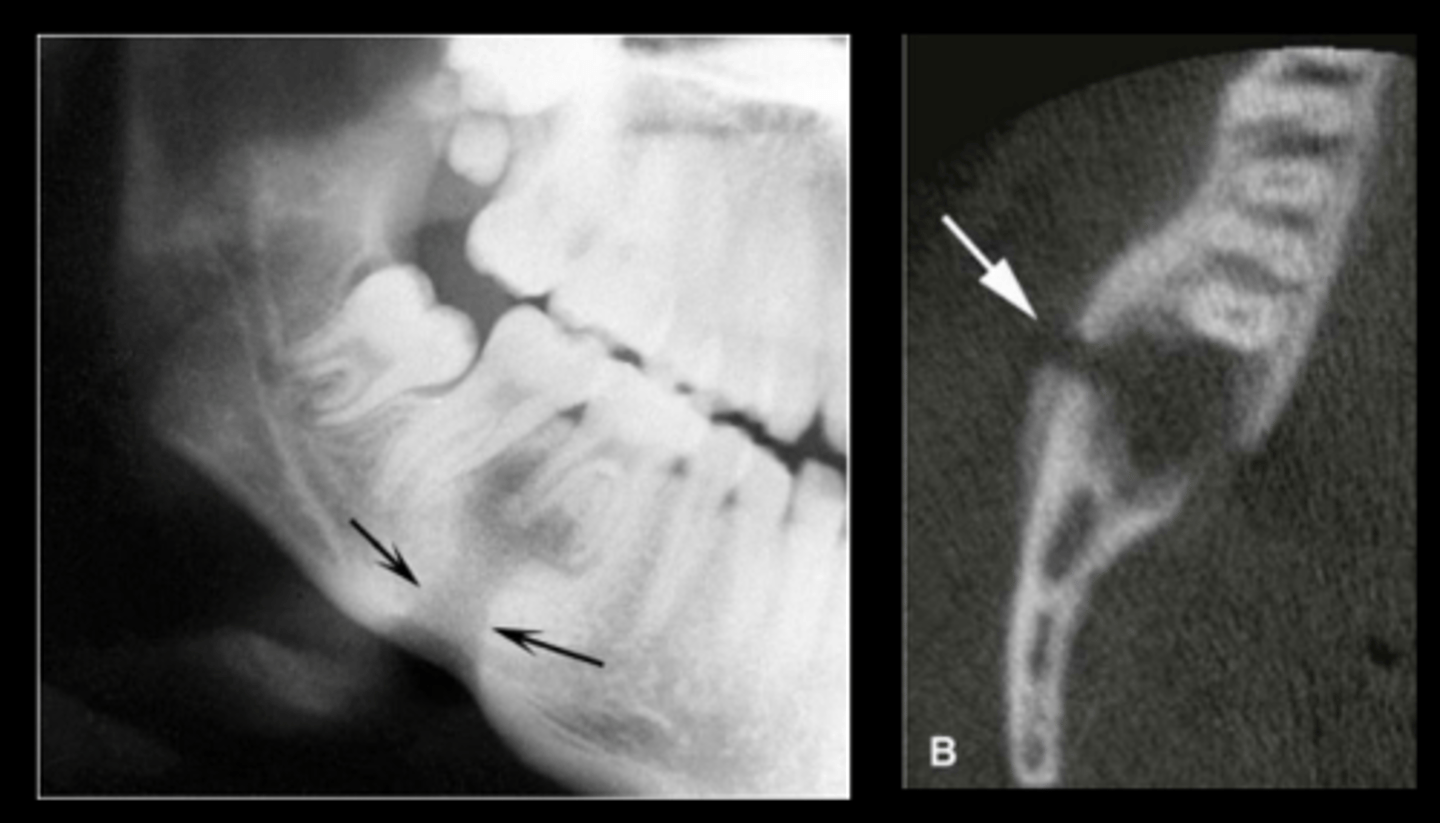

What is sequestration in chronic osteomyelitis?

Necrotic bony islands

What develops during chronic osteomyelitis?

Sinus tract

Garre's Osteomyelitis

What is a characteristic appearance of Garre's Osteomyelitis?

Onion skin